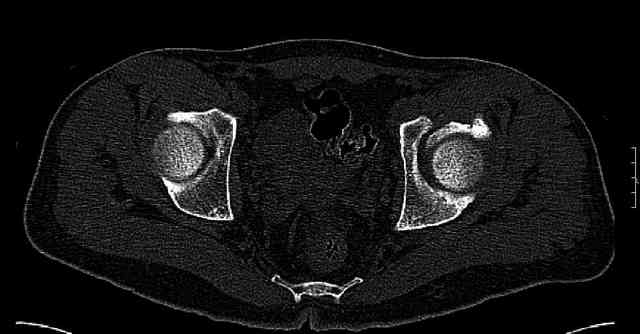

The last two images from the 3-D CT scan certainly makes the fracture look worse than the plan radiographs.

Some more images. Does it help to guess which part of the acetabulum is displaced?

Normal appearing SI joints and a healed posterior column limb... my bet's on caudal segment displacement.